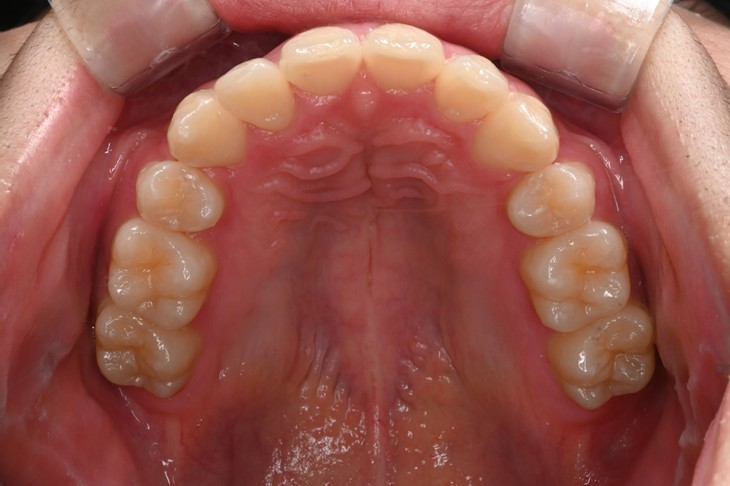

症例3:出っ歯が気になる

| 患者様データ | 20代 女性 |

| 来院主訴 | 出っ歯が気になる。 |

| 治療内容 | 出っ歯を治すために上の小臼歯を2本抜歯し、インビザラインにてマウスピース矯正を開始しました。かみ合わせを整えるためにゴムかけを行いました。 |

| 概算治療費 | 約85万円 |

| 治療期間 | 1年4ヶ月 |

| 通院回数 | 8回 |